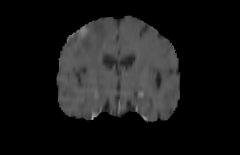

Objectives: This work aims to explore the impact of multicenter data heterogeneity on deep learning brain metastases (BM) autosegmentation performance, and assess the efficacy of an incremental transfer learning technique, namely learning without forgetting (LWF), to improve model generalizability without sharing raw data. Materials and methods: A total of six BM datasets from University Hospital Erlangen (UKER), University Hospital Zurich (USZ), Stanford, UCSF, NYU and BraTS Challenge 2023 on BM segmentation were used for this evaluation. First, the multicenter performance of a convolutional neural network (DeepMedic) for BM autosegmentation was established for exclusive single-center training and for training on pooled data, respectively. Subsequently bilateral collaboration was evaluated, where a UKER pretrained model is shared to another center for further training using transfer learning (TL) either with or without LWF. Results: For single-center training, average F1 scores of BM detection range from 0.625 (NYU) to 0.876 (UKER) on respective single-center test data. Mixed multicenter training notably improves F1 scores at Stanford and NYU, with negligible improvement at other centers. When the UKER pretrained model is applied to USZ, LWF achieves a higher average F1 score (0.839) than naive TL (0.570) and single-center training (0.688) on combined UKER and USZ test data. Naive TL improves sensitivity and contouring accuracy, but compromises precision. Conversely, LWF demonstrates commendable sensitivity, precision and contouring accuracy. When applied to Stanford, similar performance was observed. Conclusion: Data heterogeneity results in varying performance in BM autosegmentation, posing challenges to model generalizability. LWF is a promising approach to peer-to-peer privacy-preserving model training.